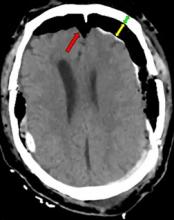

Acute post-surgical pneumocephalus is frequent in patients with cranioencephalic pathology operated on in the supine and prone position. The distribution and degrees of pneumocephalus may be related to sex, the type of cranioencephalic pathology, and the depth of the surgical lesion.